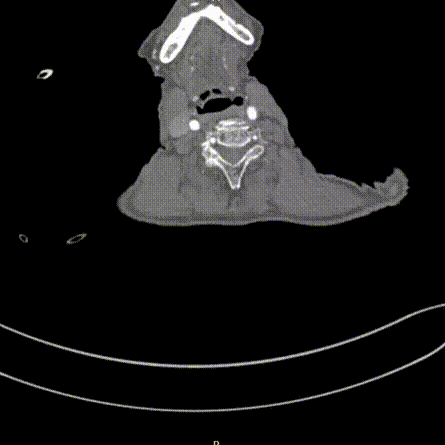

5. 穿刺点常规消毒铺巾,穿刺左右桡动脉、左右股动脉,分别置入6Fr动脉鞘,注射肝素3000u,经右侧桡动脉送入TRG多投照位行CAG,结果示:冠状动脉粥样硬化伴轻度狭窄。

6.再送入Pigtail导管胸主动脉造影:主动脉弓见一巨大瘤样突出,降主动脉见2处瘤样扩张,与CT一致。